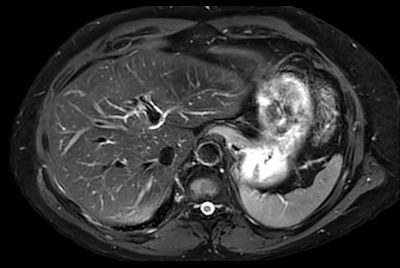

SmartSpeed Liver